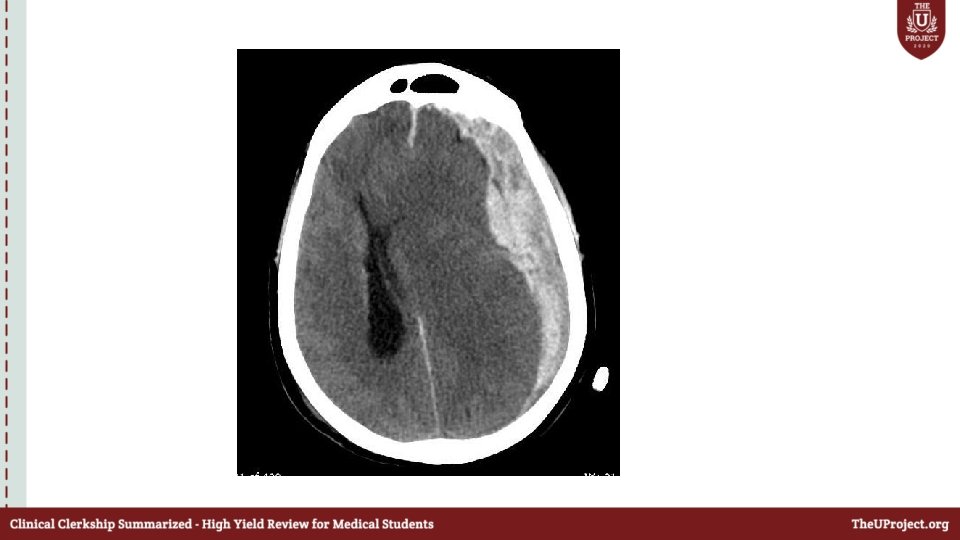

Case 2 • 35 year old male patient was hit by his wife on the head by a metallic pan ; lost consciousness and was brought by EMS to the ED. • As a trauma team leader what will you do before the patient arrives to ED ? • How will you approach this patient ?

Primary survey A: C-spine collar ON Not responding Mouth –full of blood What will you do next ? B: equal air entry bilaterally , SPO 2 100% C: BP 80/60 ; HR 60

• D : GCS: 6 E-1 V-1 M-4 Right pupil was dilated E: No other injuries identified

Secondary survey • Normal • What will you do next ?

• What are the signs of raised ICP?

• How will you mainatain the cerbral perfusion pressure ?